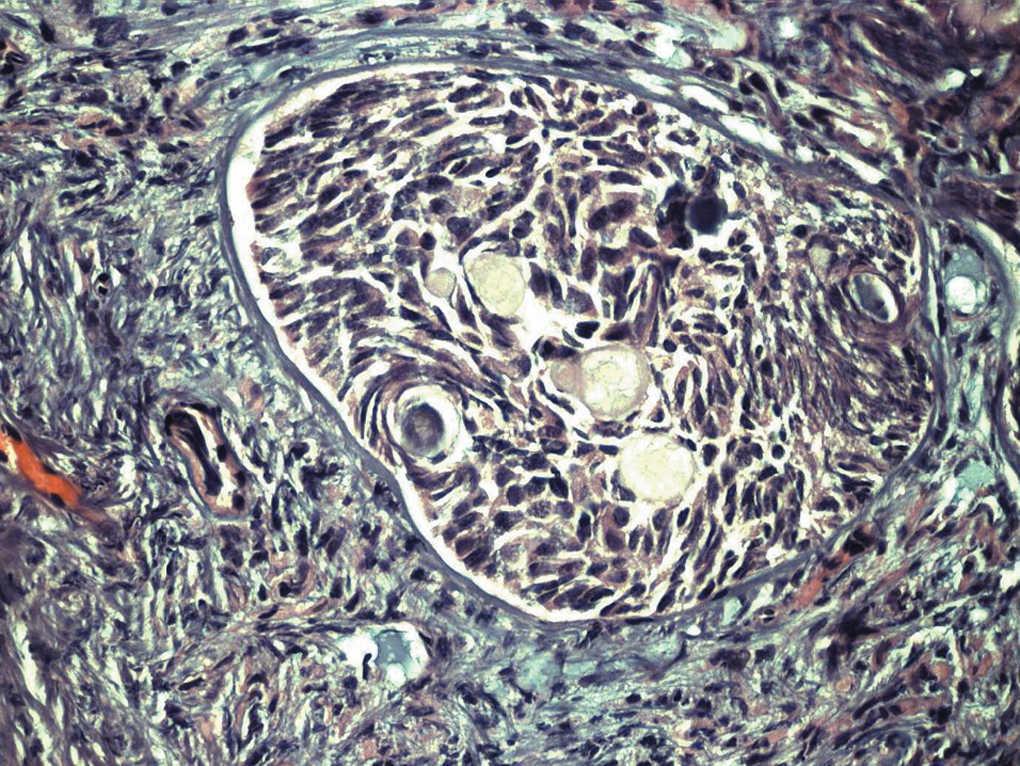

Paciente de 13 años de edad, sin antecedentes personales o familiares de interés. Estadio de Tunner P2-3 y T4, sin menarquia, talla de 1,77 cm y peso 63 kg, que consulta por aumento del perímetro abdominal con dolor. Se describe, tras el estudio de imagen, una tumoración sólida de 13 cm, con evidentes calcificaciones, dependiente de anejo derecho; ascitis a tensión. No presenta adenopatías (fig. 1). En estudios analíticos presenta BHCG de 94,9 mU/ml y perfil hormonal prepúber. Se practicó una laparotomía urgente y se halló una tumoración ovárica derecha de 10 cm, con una cápsula íntegra. El útero y el anejo izquierdos eran normales para edad de la paciente. El diagnóstico intraoperatorio fue tumor de los cordones sexuales-estroma sospechoso de células Sertoli-Leyding. Se le practicó una anexectomía derecha, una omentectomía, una apendicectomía y una biopsia de ovario contralateral más lavados peritoneales. El resultado definitivo de anatomía patológica fue de disgerminoma (fig. 2) para el ovario derecho, gonadoblastoma (fig. 3) para la biopsia del izquierdo, y el líquido peritoneal fue negativo a células malignas. La paciente recibió tratamiento adyuvante con 4 ciclos de bleomicina, etopósido y cisplatino. En la revisión posquimioterapia en nuestra consulta la paciente presentaba: fenotipo femenino normal, genitales externos normales, himen íntegro, vagina de 9 cm de longitud. Los estudios de imagen y los marcadores tumorales analíticos fueron normales, incluido el BHCG. El perfil gonadal prepúber. El estudio del cariotipo desveló un 46XY con gen SRY sin alteraciones, lo cual motivó nuestra propuesta para la gonadectomía izquierda, que se realizó por laparoscopia, y se encontró un resultado anatomopatológico de cintilla gonadal normal. La paciente comenzó un tratamiento con estroprogestágenos cíclicos. Actualmente, se encuentra eumenorreica, libre de enfermedad y con fenotipo femenino P4-T4.

Figura 2. Disgerminoma.